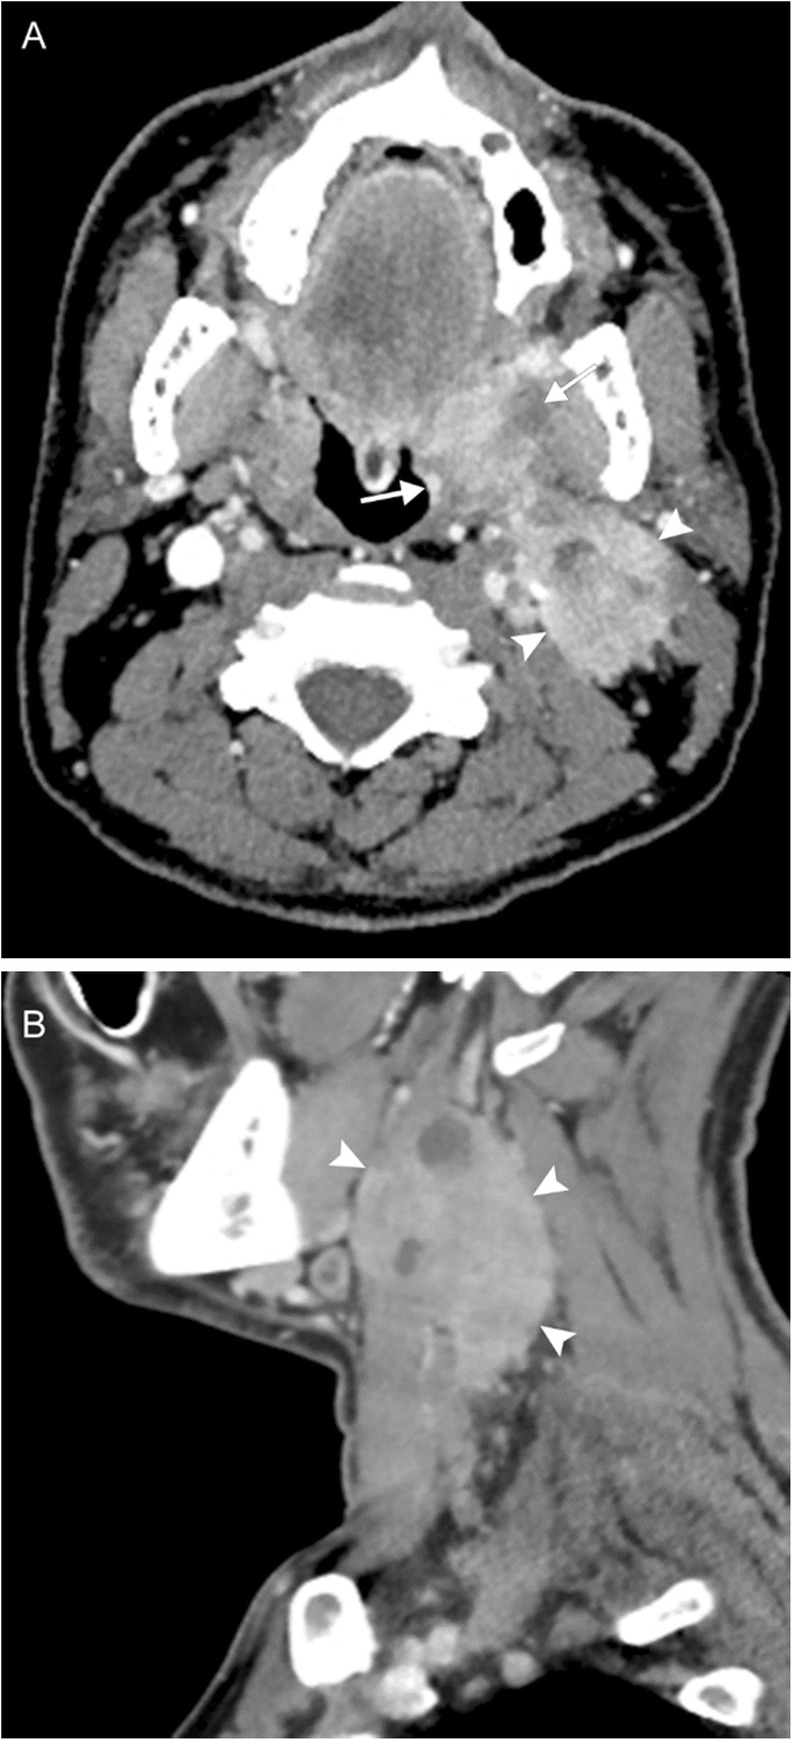

Fig. 7.

Oropharyngeal squamous cell carcinoma. A 40-year-old man presenting with tender neck mass, dysphagia to solid food, odynophagia, and voice changes. Axial (a) and sagittal (b) contrast-enhanced CT images reveal an enhancing mass at the left oropharynx (arrows) and extensive left-sided lymphadenopathy, including a large level II nodal conglomerate with central areas of necrosis (arrowheads). Biopsy revealed this to be human papilloma virus (HPV)-mediated squamous cell carcinoma. Voice change was attributed to encroachment upon the carotid space resulting in vagal nerve irritation.